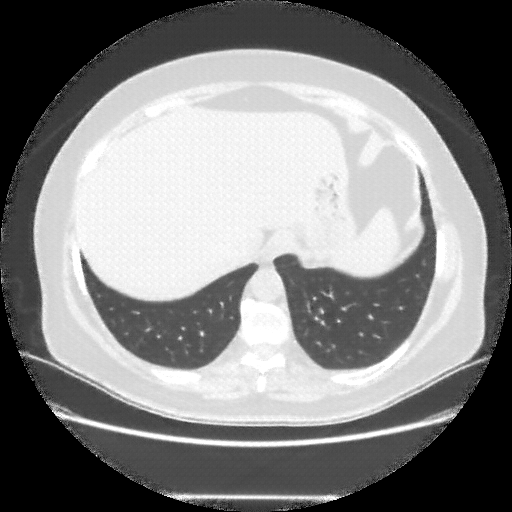

Original NATIVE CT scan (input)

Full window (WL 1023.5, WW 4095 β†’ Low βˆ’1024, High +3071)

Lung window (WL -600, WW 1500 β†’ Low βˆ’1350, High +150)

Mediastinum window (WL 40, WW 400 β†’ Low βˆ’160, High +240)